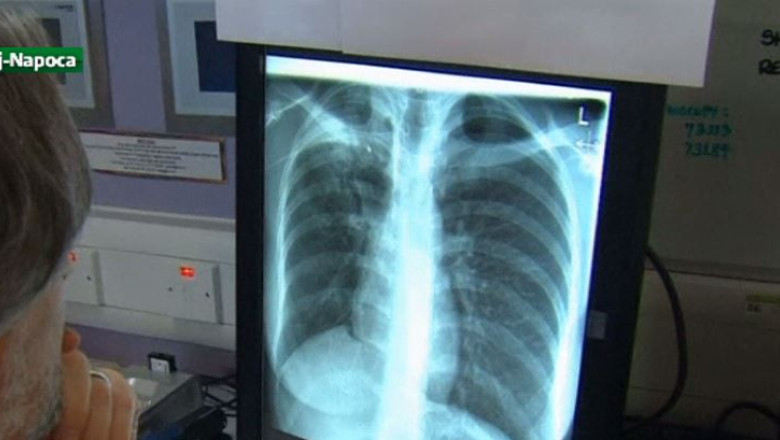

"Metastazele pulmonare sunt cele mai frecvente în majoritatea cancerelor și până acum acești pacienți nu aveau nici o șansă. Aceste metastaze existente în plămân cresc și înlocuiesc plămânul, iar pacientul ajunge în faza în care să moară", a afirmat Dan Nicolau, şeful Secţiei de Chirurgie toracică.

Până acum, 70 de pacienți care se aflau în stadii avansate de boală au beneficiat de acest tip de intervenţie, care nu îi poate vindeca, însă le prelungeşte viaţa, în medie, cu doi ani. Aparatul laser este unic în Romania şi a fost cumpărat anul trecut din Germania.